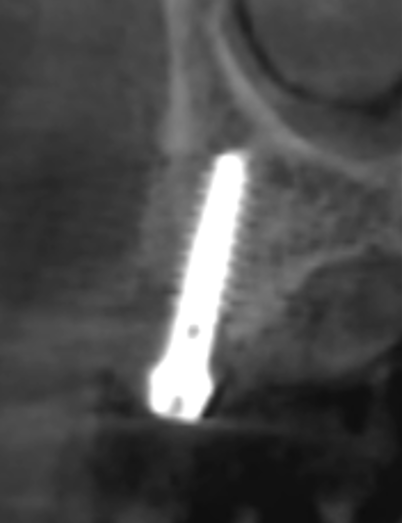

#14 부위에 식립된 Magi Core와 협측으로 골이식이 된 것을 CT에서 확인할 수 있다 [그림 7].